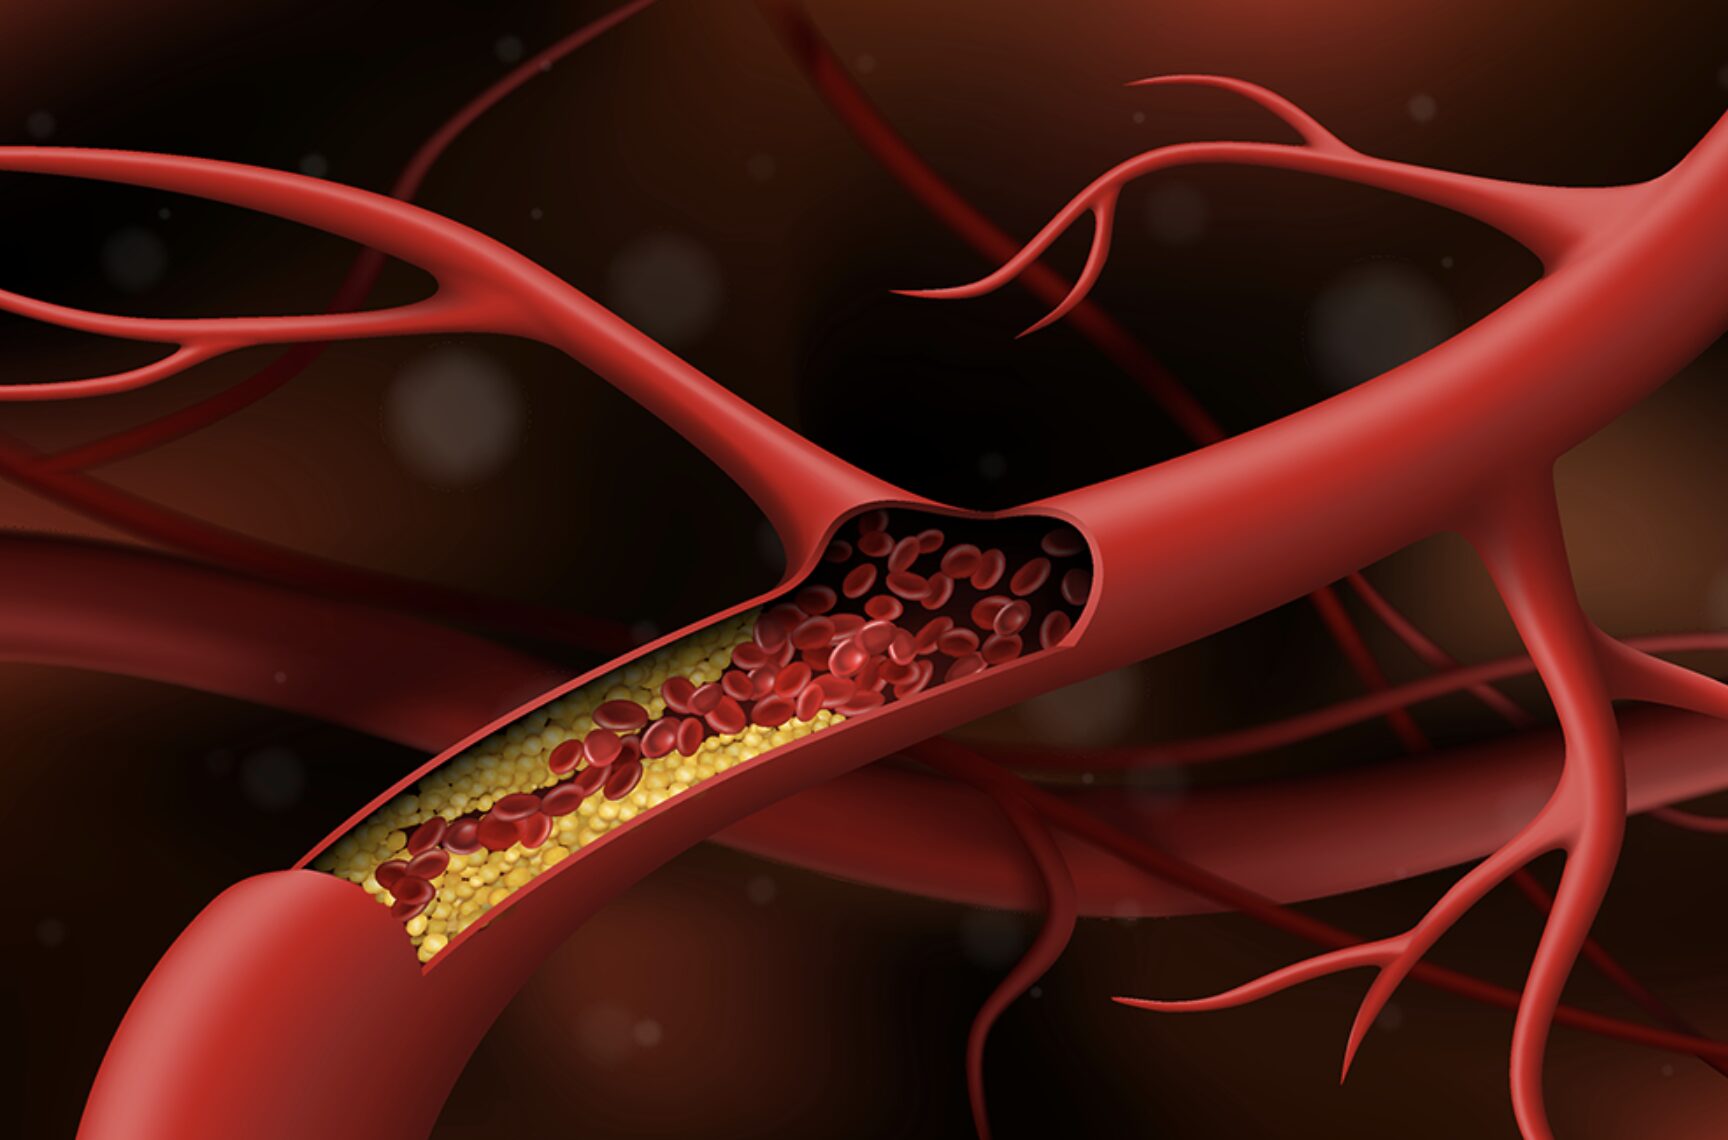

Đột quỵ trẻ hóa: Nghiên cứu tiết lộ nguyên nhân bất ngờ ở thanh thiếu niên

Đột quỵ vốn được xem là bệnh lý của người trung niên và cao tuổi, nhưng những năm gần đây, căn bệnh này đang có xu hướng trẻ hóa đáng lo ngại. Một nghiên cứu vừa công bố trên tạp chí Nutrients đã chỉ ra những nguyên nhân bất ngờ khiến thanh thiếu niên đối mặt với nguy cơ đột quỵ và bệnh tim mạch ngày càng sớm.